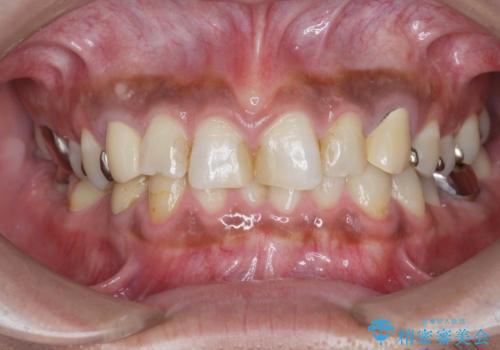

複数箇所コンポジット充填された前歯をセラミック治療

- コンポジットレジンの充填箇所がすり減ってしまい、形の悪くなった前歯の治療を希望され来院されました。

充填部位が大きく、再度充填をするには神経と近くなり抜髄のリスクが高まるため、劣化の少ないセラミックでフルカバーするセラミッククラウン治療を行うこととしました。